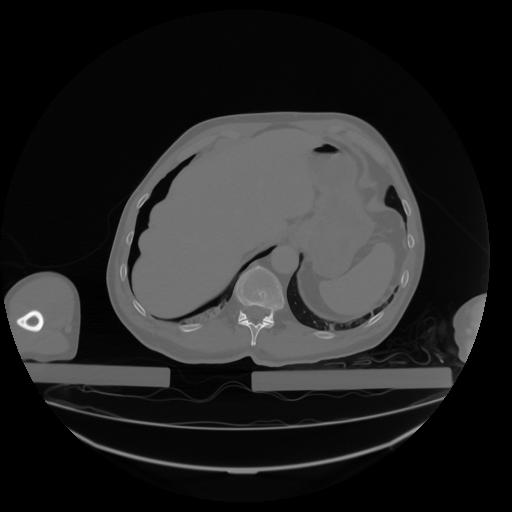

27 CUERPO,CE,Axial,3.0,CUERPO,,